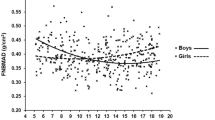

For BMD, men showed early significant bone loss before midlife (Fig. 1A). Compared to the reference age group, BMD in the 30–39 years age group already had significantly lower values (−7.8 %, p < 0.001). From the third decade, significant loss in BMD continued across all groups. However, in women, BMD loss began in the fifth decade and continued over the rest of the lifetime, accelerating during the postmenopausal period. Before the seventh decade, the mean percentage changes from the reference group in each decade were greater in men than they were in women (−7.80 % vs. −1.98 % in the fourth decade; −12.16 % vs. −2.81 % in the fifth decade; −15.57 % vs. −10.13 % in the sixth decade; p < 0.001 for all). However, from the eighth decade and onward, women showed steeper changes from the reference values than did men (−26.32 % vs. −28.91 % in the eighth decade, p < 0.05; −28.13 % vs. −37.58 % in the ninth decade, p < 0.001). Consequently, 71.87 % of the reference value for men and only 62.42 % for women remained in the oldest group. The essential trends of CSA were coincident with BMD changes in both genders (Fig. 1B).

Age trends in bone mineral density (BMD) (A) and cross-sectional area (CSA) (B) at the femur neck. a Trends for men. b Trends for women. a’ p < 0.05, a’’ p < 0.01, a’’’ p < 0.001 compared with the reference group (19–29 years of age); b’ p < 0.05, b’’ p < 0.01, b’’’ p < 0.001 compared with the previous age group. c Mean percentage changes from the mean values of the reference group (19–29 years of age) in each age group. a’ p < 0.05, a’’ p < 0.01, a’’’ p < 0.001, men compared with women. BMD bone mineral density, CSA cross-sectional area

Mean values of cortical thickness (A) and width (FNW) (B) at the femur neck in men (a) and women (b) are shown in Fig. 2. Age trends of cortical thickness were similar for BMD and CSA in men, in whom significant loss (−8.41 %, p < 0.001) of cortical thickness was already noted in the fourth decade; significant loss continued to be shown in all decades thereafter. However, in women, no significant difference was observed in the 30–39 years age group compared to that of the reference decade. In women, statistically significant cortical thinning began in the fifth decade, with a relatively constant subsequent rate of loss thereafter. Before the seventh decade, the amount of decrease was also much greater in men than in women (−8.41 % vs. −2.15 % in the fourth decade; −13.08 % vs. −2.68 % in the fifth decade; and −16.35 % vs. −10.75 % in the sixth decade; p < 0.001 for all). However, by the eighth decade, the rate of decline in the cortical thickness in women was steeper than that seen in men (−27.57 % vs. −30.64 % in the eighth decade, p < 0.05; −29.43 % vs. −39.24 % in the ninth decade, p < 0.001). In the patterns of FNW according to age, we observed more changes in women and fewer changes in men. Significantly higher values of FNW compared to the reference value were observed only in the fifth (+2.01 %, p < 0.05), sixth (+1.84 %, p < 0.05), and seventh decades (+1.87 %, p < 0.05) for men, but there were no significant differences in any other decade-to-decade comparisons. However, in women, the mean values of FNW in all other decade groups were higher than that of the reference decade, and the degrees of increase were larger than those seen in men. Nonetheless, no other additional, significant changes occurred in women after the fourth decade. Consequently, the significant widening of FNW across entire decades was 2.7 fold larger in women than it was in men (+1.87 % vs. +4.94 %, p < 0.05).

Age trends in cortical thickness (A) and width (B) at the femur neck. a Trends for men. b Trends for women. a′ p < 0.05, a′′ p < 0.01, a′′′ p < 0.001 compared with the reference group (19–29 years of age); b′ p < 0.05, b′′ p < 0.01, b′′′ p < 0.001 compared with the previous age group. c Mean percentage changes from the mean values of the reference group (19–29 years of age) in each age group. a′ p < 0.05, a′′ p < 0.01, a′′′ p < 0.001, men compared with women

Trends of the femur strength marker, cross-sectional moment of inertia (CSMI) (A), section modulus (B), and BR (C) at the femur neck in both genders along with the mean percentage changes from the reference values (c), are provided in Fig. 3. Until the fifth decade, there were no significant changes of CSMI in men. Statistically significant decreases occurred thereafter, with acceleration observed for men in their eighth decade. However, in women, the mean value in the fifth decade was 8.46 % higher than the reference value, and a significant decrease began thereafter, reaching a value 26.46 % lower than that of the reference in the oldest group. The mean percentage decreases from the reference group in the sixth and seventh decade were larger in men, and these decreases were greater in women only for those in their ninth decade (−8.01 % vs. +2.66 % in the sixth decade, p < 0.001; −10.95 % vs. −7.06 % in the seventh decade, p < 0.01; and −19.64 % vs. −26.46 % in the ninth decade, p < 0.01).

Age trends in cross-sectional moment of inertia (CSMI) (A), section modulus (B), and buckling ratio (BR) (C) at the femur neck. a Trends for men. b Trends for women. a′ p < 0.05, a′′ p < 0.01, a′′′ p < 0.001 compared with the reference group (19–29 years of age); b′ p < 0.05, b′′ p < 0.01, b′′′ p < 0.001 compared with the previous age group. c Mean percentage changes from the mean values of the reference group (19–29 years of age) in each age group. a′ p < 0.05, a′′ p < 0.01, a′′′ p < 0.001, men compared with women

For trends of section modulus, there were greater reductions with age in both genders, but the patterns differed between them. Essentially, the entire decline in neck section modulus of women occurred at the sixth decade and beyond; paradoxically, a more apparent decline occurred before this age in male participants. In age trends of BR at the femur neck, we observed significant changes across all decade groups, but the patterns were quite different according to gender. BR in men already showed apparent increases starting at the fourth decade, with consistently slow rates across all decades. However, in women, no significant increase was observed until the fourth decade, with steeper increases occurring thereafter. As a result, BRs in the oldest groups increased by 51.91 % in men and by 94.93 % in women compared to the reference values. In age trends with HAL and NSA, we did not observe any significant changes according to age group (data not shown).